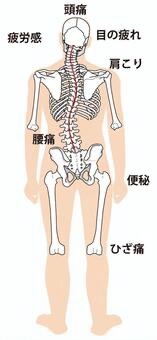

腰の炎症からくる膝の痛み

腰から出ている神経は足の方につながっています。

そして、腰への負担が続いて腰に炎症が起きると、膝に痛みとして現れる場合があります。

実際の臨床では割とこのパターンも多いと感じています。

このような方は腰の炎症を取り除く施術をしないと、改善するのは難しいと考えています。